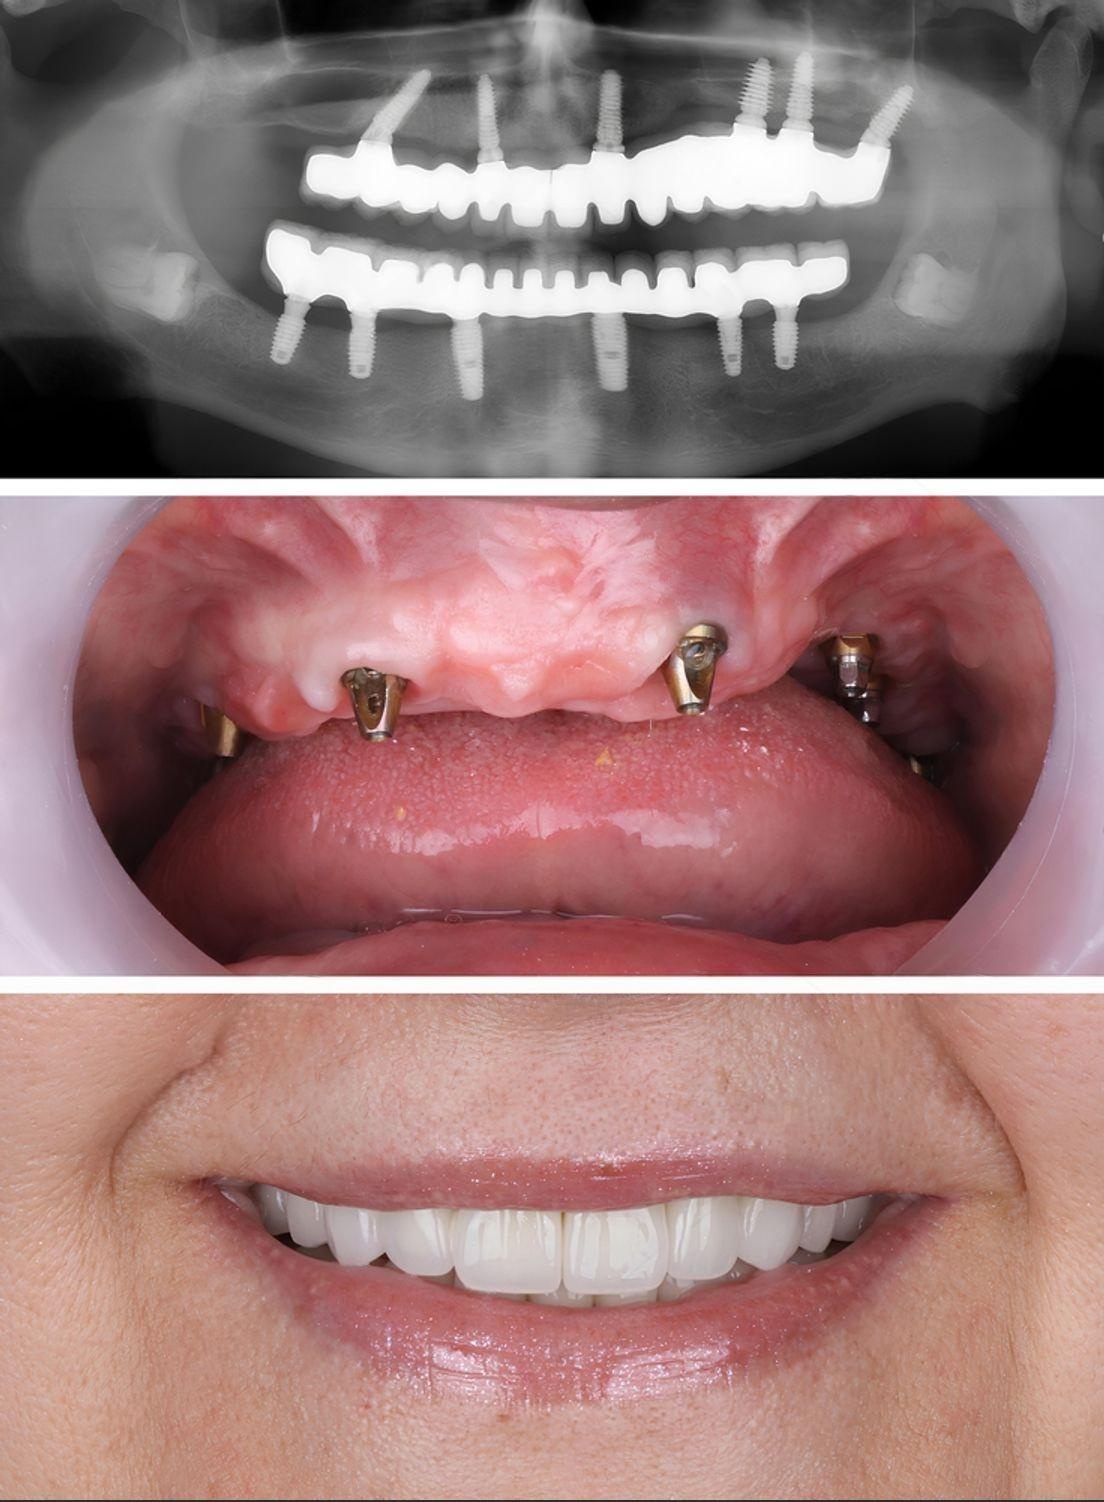

Real Results. Real Confidence.

At Al Rayashi Dental Center, we believe that every smile tells a story — and we’re proud to be part of so many incredible journeys. Our Smile Transformations page showcases real patients who have trusted us to restore their confidence and enhance their dental health.

From subtle refinements to dramatic changes, these before-and-after cases highlight the power of expert care and advanced dental technology.

Smile Transformations